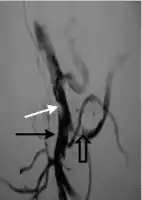

.png)

Portal vein thrombosis affects the hepatic portal vein, which can lead to portal hypertension and reduction of the blood supply to the liver.[5] It usually happens in the setting of another disease such as pancreatitis, cirrhosis, diverticulitis or cholangiocarcinoma.[6]